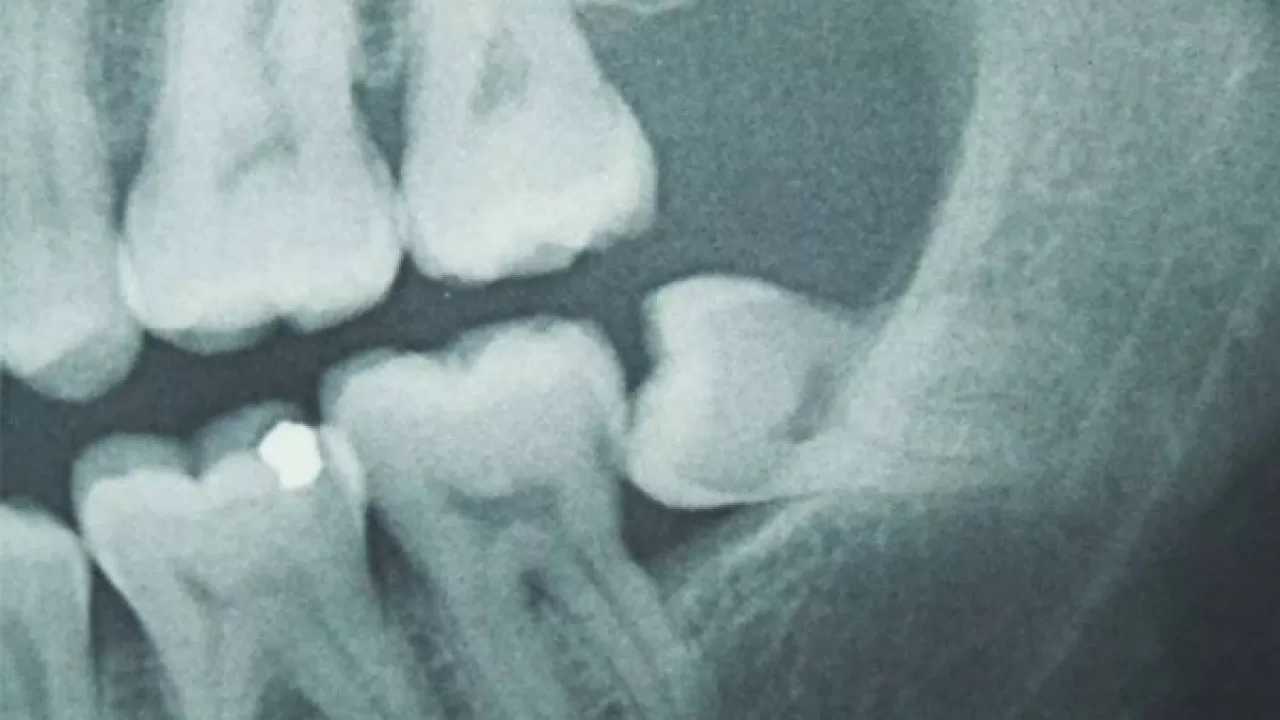

Ученые проанализировали данные 1255 пациентов, которые на протяжении двух десятилетий регулярно проходили тесты на чувствительность к вкусам. Среди них 891 человек перенес удаление зубов мудрости, а у остальных зубы остались.

Результаты исследования показали, что у тех, кому удаляли третьи моляры, способность различать вкусы оказалась на 3–10% выше. В одном из тестов участники должны были определить вкус растворов сахарозы, соли, лимонной кислоты и кофеина в различных концентрациях. Люди без зубов мудрости заметно лучше справились с этой задачей, особенно женщины.

Точные причины этого явления пока остаются неясными. Исследователи предполагают, что удаление зубов мудрости может повредить нервные окончания вкусовых рецепторов в передней части полости рта. В ответ на это чувствительность других рецепторов со временем усиливается.